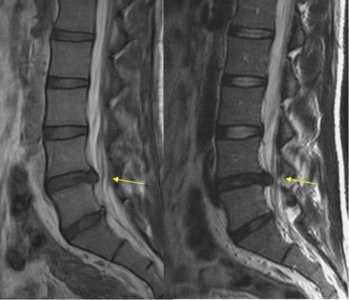

Resonancia magnética o una tomografía computarizada de la columna para mostrar en qué parte del canal espinal está presionando la hernia discal, así como para evaluar ligamentos, y tejidos blandos profundos, descartar tumoraciones y otras causas poco frecuentes de dolor.